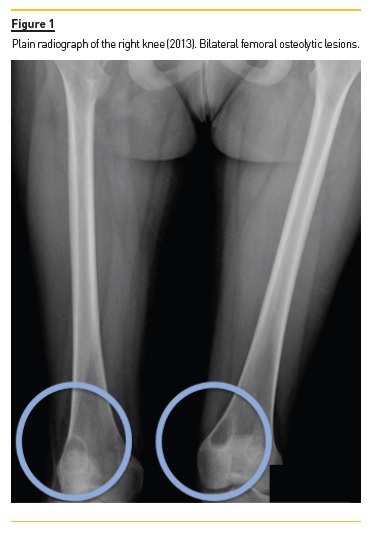

Four years later (2017), asymptomatic bone tumefactions of the knees were observed and imagiological re-evaluation was performed (Fig. 3 and 4), revealing expansion and esclerosis of previous lesions involving right iliac bone, distal femurs and right proximal tibia, as well as a new sacrum lesion. Bone scintigraphy confirmed hypermetabolic lesions and a subtotal parathyroidectomy was then performed.